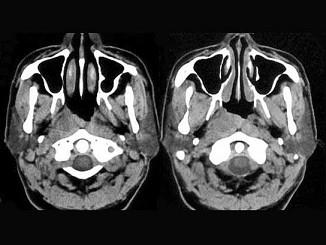

问题 男,52岁,右耳鸣两月余,伴鼻塞,CT如图所示,应诊断为 ( )

选项 A、鼻咽癌 B、鼻咽部慢性炎症 C、鼻咽纤维血管瘤 D、增殖体肥大 E、鼻咽淋巴瘤

答案 A